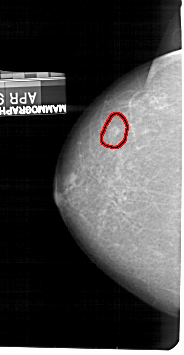

A_1435_1.LEFT_MLO

LEFT_MLO LINES 4936 PIXELS_PER_LINE 2746 BITS_PER_PIXEL 12 RESOLUTION 43.5 OVERLAY

FILE: A_1435_1.LEFT_MLO.OVERLAY

TOTAL_ABNORMALITIES 1

ABNORMALITY 1

LESION_TYPE MASS SHAPE OVAL MARGINS ILL_DEFINED

ASSESSMENT 4

SUBTLETY 3

PATHOLOGY BENIGN

TOTAL_OUTLINES 1

BOUNDARY